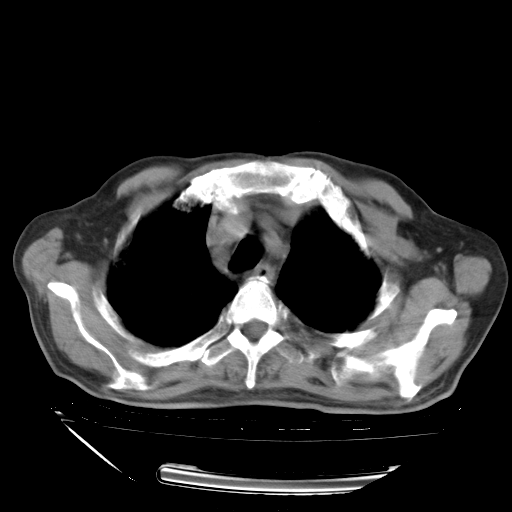

甲强龙80mg/日+抗结核治疗(异烟肼+利福霉素+乙胺丁醇)10天。复查肺部CT。